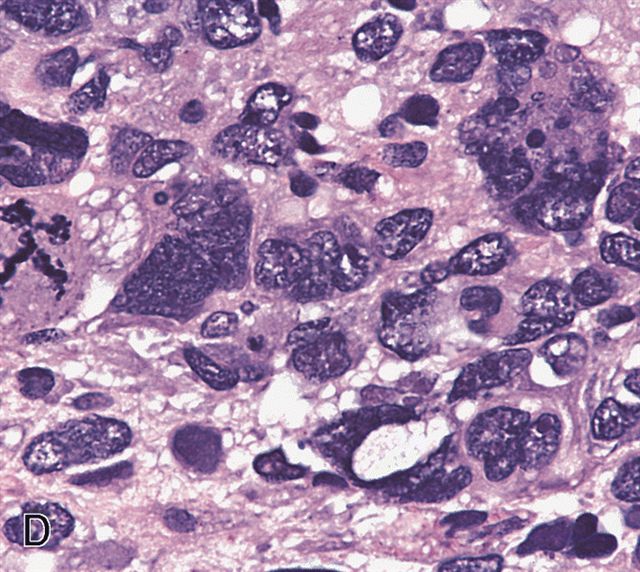

AFIP images - anaplastic rhabdomyosarcoma

- Anaplasia is defined similar to anaplastic Wilms tumor as a significant nuclear variation (cells that are 3x larger than background tumor cells) and the presence of atypical multipolar mitotic figures

- It was historically a negative prognostic factor but this may no longer be true (Cancer 2008;113:3242, Eur J Cancer 2021;143:127)

- Anaplastic tumors often require more intensive treatment (Cancer 2008;113:3242)

- Anaplasia specifically requires multipolar mitotic figures

- Make sure you are not overinterpreting degenerating or apoptotic cells

- Look for organization of the division and exclude cells that appear to be exploding

- Also try to avoid interpreting overlapping cells as 1 larger cell

A. 3x nuclear size variability and tripolar mitotic figures. Multipolar mitotic figures (including tripolar mitoses) and nuclear anaplasia (3x variation in nuclear size) are required to diagnose anaplastic embryonal rhabdomyosarcoma (ERMS). Solid growth pattern is irrelevant and necrosis can be seen in any subtype of rhabdomyosarcoma. ERMS typically displays the alternating pattern of hypocellularity and hypercellularity (also a buzzword for high grade malignant peripheral nerve sheath tumors). There is no requirement for a specific mitotic rate.